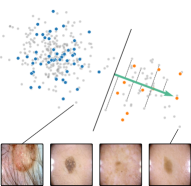

Alternatively, inspired by RelMax, we can compute bias scores using relevance scores instead of activations, as outlined in Appendix A.2. Since relevance scores are computed class-specifically, this approach allows distinguishing concepts that are artifactual for certain classes but valid for others. An illustration is provided in Fig. 2 (left), where a CAV has been trained to distinguish between known artifact () and non-artifact samples (). This concept representation can subsequently be used to compute concept scores for unknown samples (), supporting annotators in the detection of further artifact samples.

where denotes element-wise multiplication. This yields a heatmap that can be used as a soft mask or converted to a binary segmentation mask, for instance using thresholding techniques like Otsu’s method [57]. An example is shown in Fig. 2 (right), showing soft masks as heatmaps from concept-conditioned local attribution scores, along with binary masks for three known data artifacts: rulers and band-aids for skin cancer detection, and pacemakers in chest radiographs.